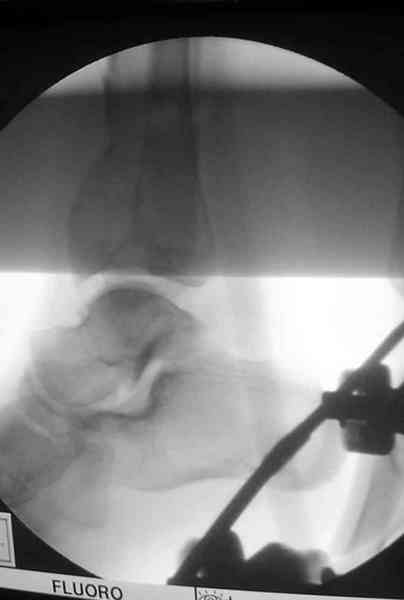

2. Второе. Следует обязательно усилить фиксацию: спицы через передний отдел стопы и пяточную кость, вторая спица через проксимальное кольцо и 1-2 стержня в проксимальный отломок б/б кости. Сроки фиксации до 8 недель. Аппаратом можно устранить, кажется, появившийся вальгус. В подобных ситуациях лучше ведут себя стержни, которыми можно сопоставить и сдавить лодыжки и задний край б/б кости. Привожу случай восстановления голеностопного сустава спустя 2,5 мес.(этап лечения) после травмы со стержнями.

3. Дистальную опору можно было бы взять в виде ¾ кольца или двух разноуровневых полуколец, соединенных небольшими стяжными стержнями. ¾ кольца - не давят на стопу, а разноуровневые полукольца «обходят» сустав. Одно снизу, другое сверху.

И вправду. В аппарате - практически идеальная для данного случая репозиция (браво!). Пластинка только помешала( в плане возможных осложений), так как не добавит стабильности после снятия наружного фиксатора, (что не скоро будет). Спицы в аппарате, пожалуй, только добавят проблем с дальнейшим лечением (проксимально - я - за стержни). Вполне приемлимо бы было, добившись репозиции в дистракторе, провести спицы с упорными под ЭОП, срепонировать отломки и оставить как есть. А вероятный артродез произвесть в аппарате потом.